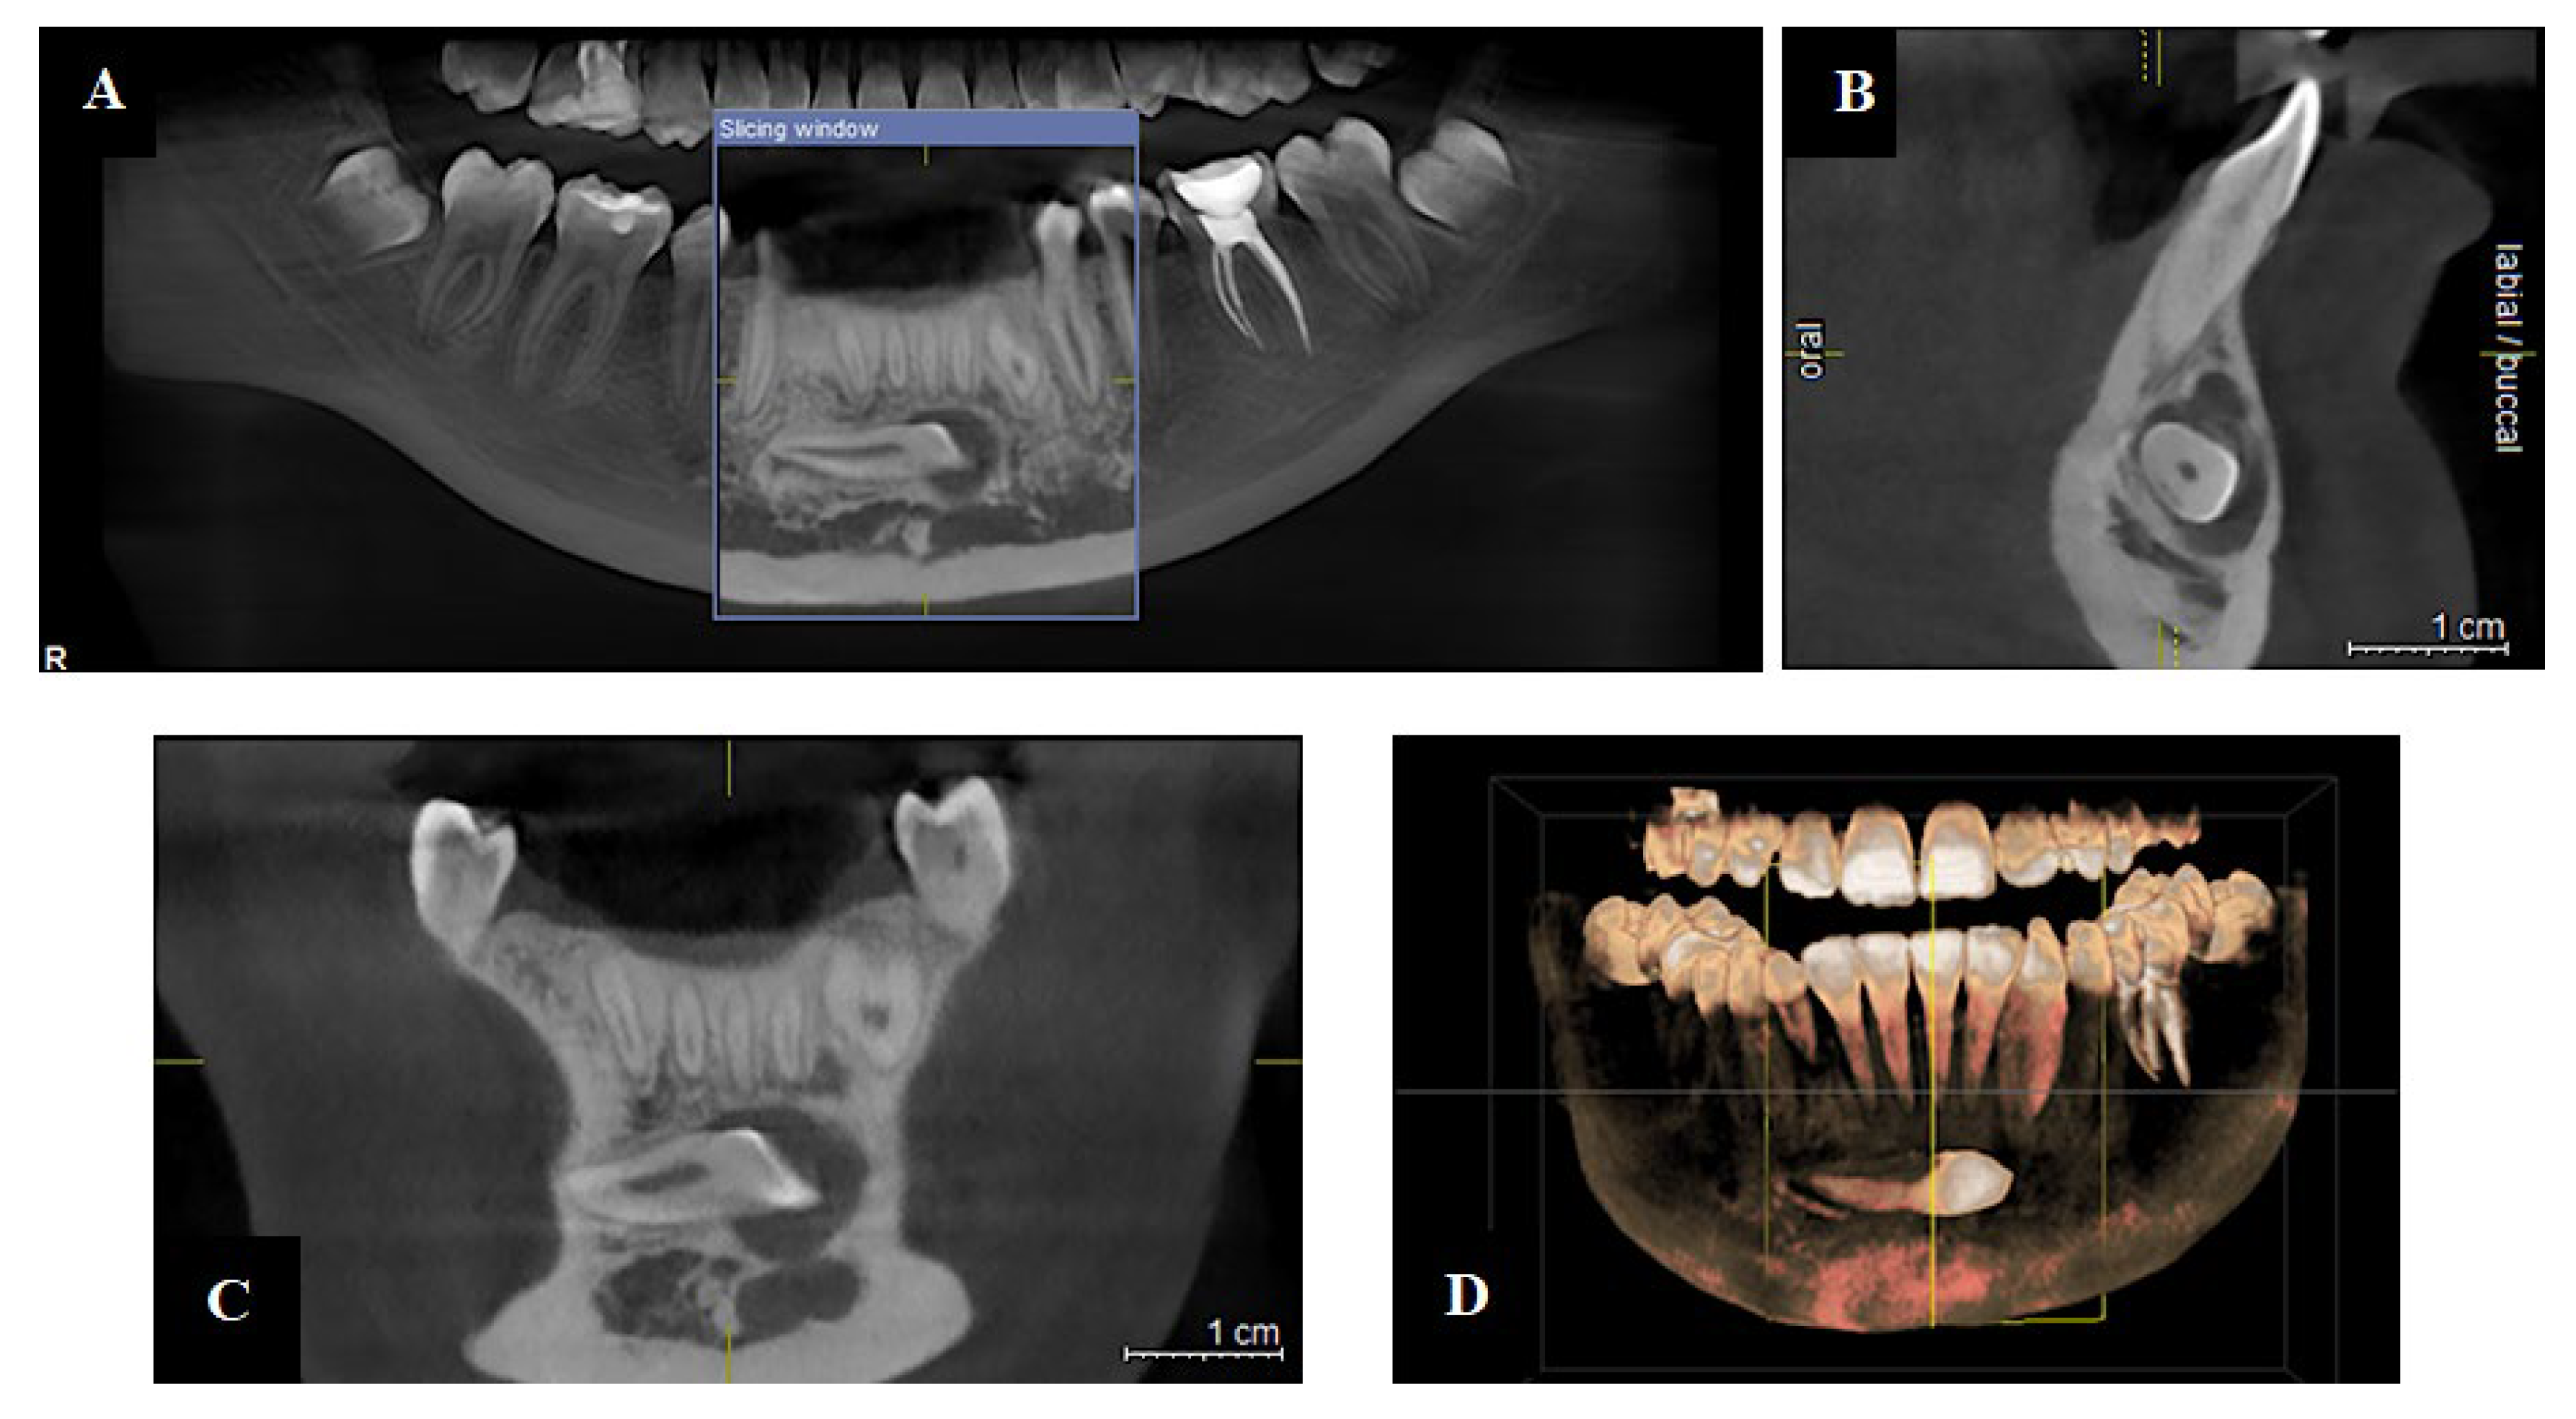

4.2. CBCT: A Foundation for 3D Visualization

5.2.1. Endodontics

5.2.2. Implantology

- Ríos-Osorio, N.; Quijano-Guauque, S.; Briñez-Rodríguez, S.; Velasco-Flechas, G.; Muñoz-Solís, A.; Chávez, C.; Fernandez-Grisales, R. Cone-Beam Computed Tomography in Endodontics: From the Specific Technical Considerations of Acquisition Parameters and Interpretation to Advanced Clinical Applications. Restor. Dent. Endod. 2023, 49, e1. [Google Scholar] [CrossRef] [PubMed]

- Saini, R.S.; Bavabeedu, S.S.; Quadri, S.A.; Gurumurthy, V.; Kanji, M.A.; Kuruniyan, M.S.; Binduhayyim, R.I.H.; Avetisyan, A.; Heboyan, A. Impact of 3D Imaging Techniques and Virtual Patients on the Accuracy of Planning and Surgical Placement of Dental Implants: A Systematic Review. Digit. Health 2024, 10, 20552076241253550. [Google Scholar] [CrossRef]

- Yepes, J.F.; Al-Sabbagh, M. Use of cone-beam computed tomography in early detection of implant failure. Dent. Clin. N. Am. 2015, 59, 41–56. [Google Scholar] [CrossRef] [PubMed]